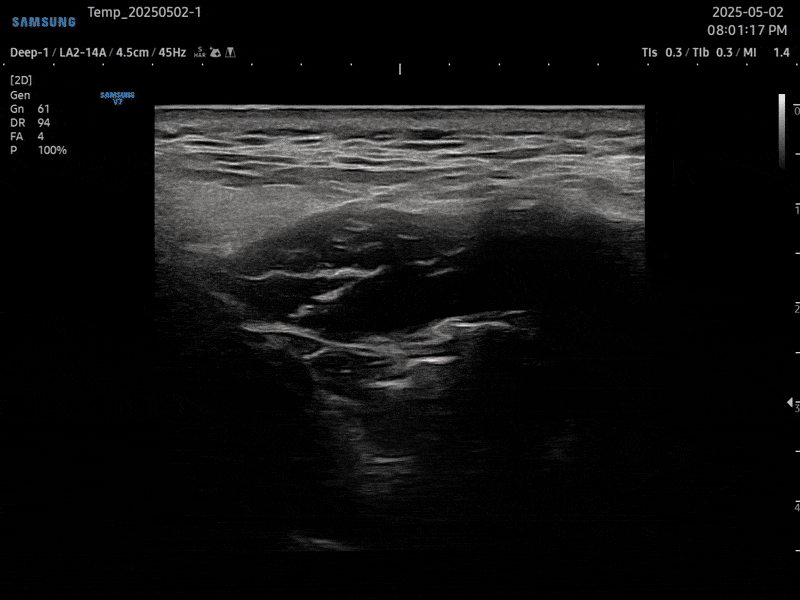

01. PDRN 약침

PDRN 약침은 인체의 DNA와 90% 이상 유사한 구조로 세포 증식을 활성화하여

손상된 조직을 복구하는 효과가 뛰어납니다. 초음파를 활용하여 신경을 압박하는

염증을 박리하고 손상된 조직을 재생합니다.